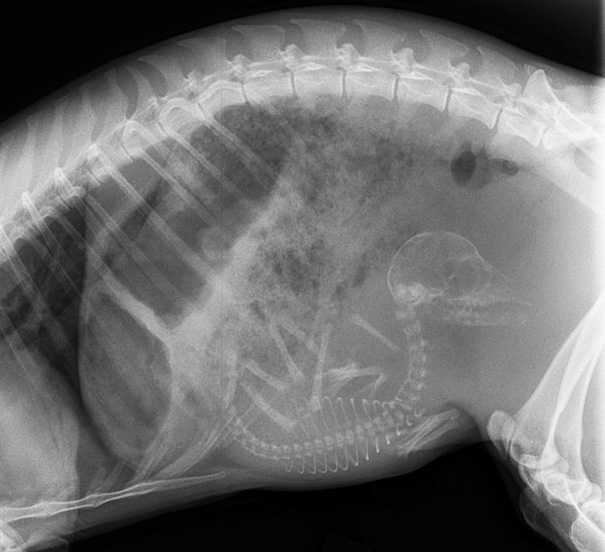

Unikāli rentgena attēli ar dzīvniekiem gaidībās

Bieži negadās publiski redzēt dzīvnieku rentgena uzņēmumus. Turklāt šie rentgena uzņēmumi ir veikti dzīvniekiem, kuri ir mazuļu gaidībās. Tagad ikvienam ir iespēja ielūkoties, kā dzīvnieku mazuļi attīstās savu mammu vēderos.